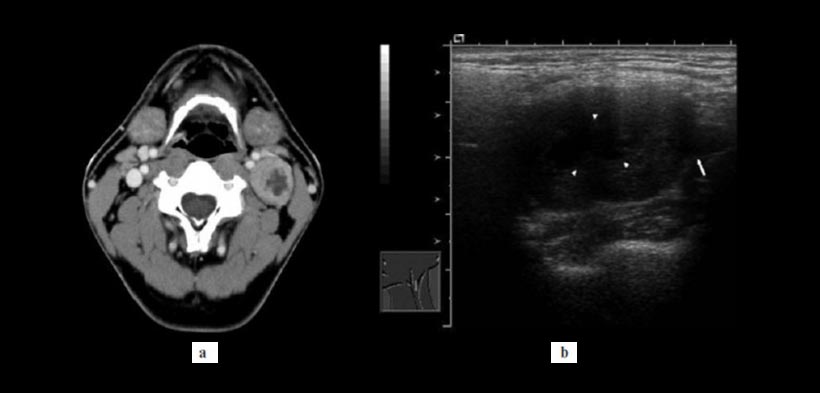

Figura 2. Paciente de sexo masculino de 41 años de edad, se había dado cuenta de una inflamación indolora en su región cervical superior izquierda hace aproximadamente 1 mes. El examen histopatológico indicó que el tumor era un schwannoma. Se osbervaron cambios quísticos, las Imágenes de la TC con contraste reveló una lesión de masa en forma redonda en la vaina carotídea izquierda con límites bien definidos y una zona homogénea de baja densidad más o menos en el centro de la masa. (a) El valor de la TC para la región central de la masa fue de aproximadamente 20 UH y de la periferia fue de 77 UH. (b) La ecografía mostró una masa que era ovoide, hipoecoica y sobre todo homogéneo con un eco interno ligero, pero no tenía región ecogénico en el centro (puntas de flecha). Imágenes Doppler de potencia no revelaron vascularización interna.